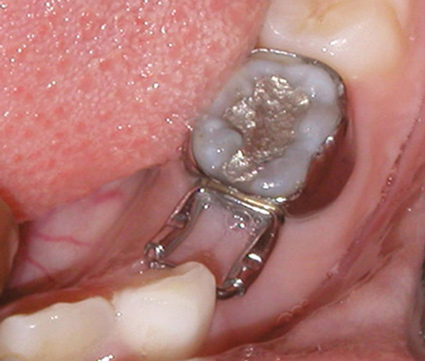

Fig 16. Lower lingual holding arch (mandible).

Figure 16

In cases of premature loss of primary teeth or missing permanent teeth, space maintenance is crucial.42 Possible causes of such tooth loss include caries, trauma, or a congenital disorder. If proper spacing is not maintained, mesial tooth drift may occur,43,44 which can lead to impaction or ectopic eruption of permanent teeth, as previously discussed. Various designs of space maintainers are available, depending on the location in the mouth that needs space preservation. Common devices include the Nance arch for the maxilla (Figure 15), a lower lingual holding arch for the mandible (Figure 16), and a band and loop or distal shoe for unilateral cases of space loss (Figure 17). Band and loop appliances seem to have the highest longevity intraorally; generally, unilateral devices fare better than their bilateral counterparts.45